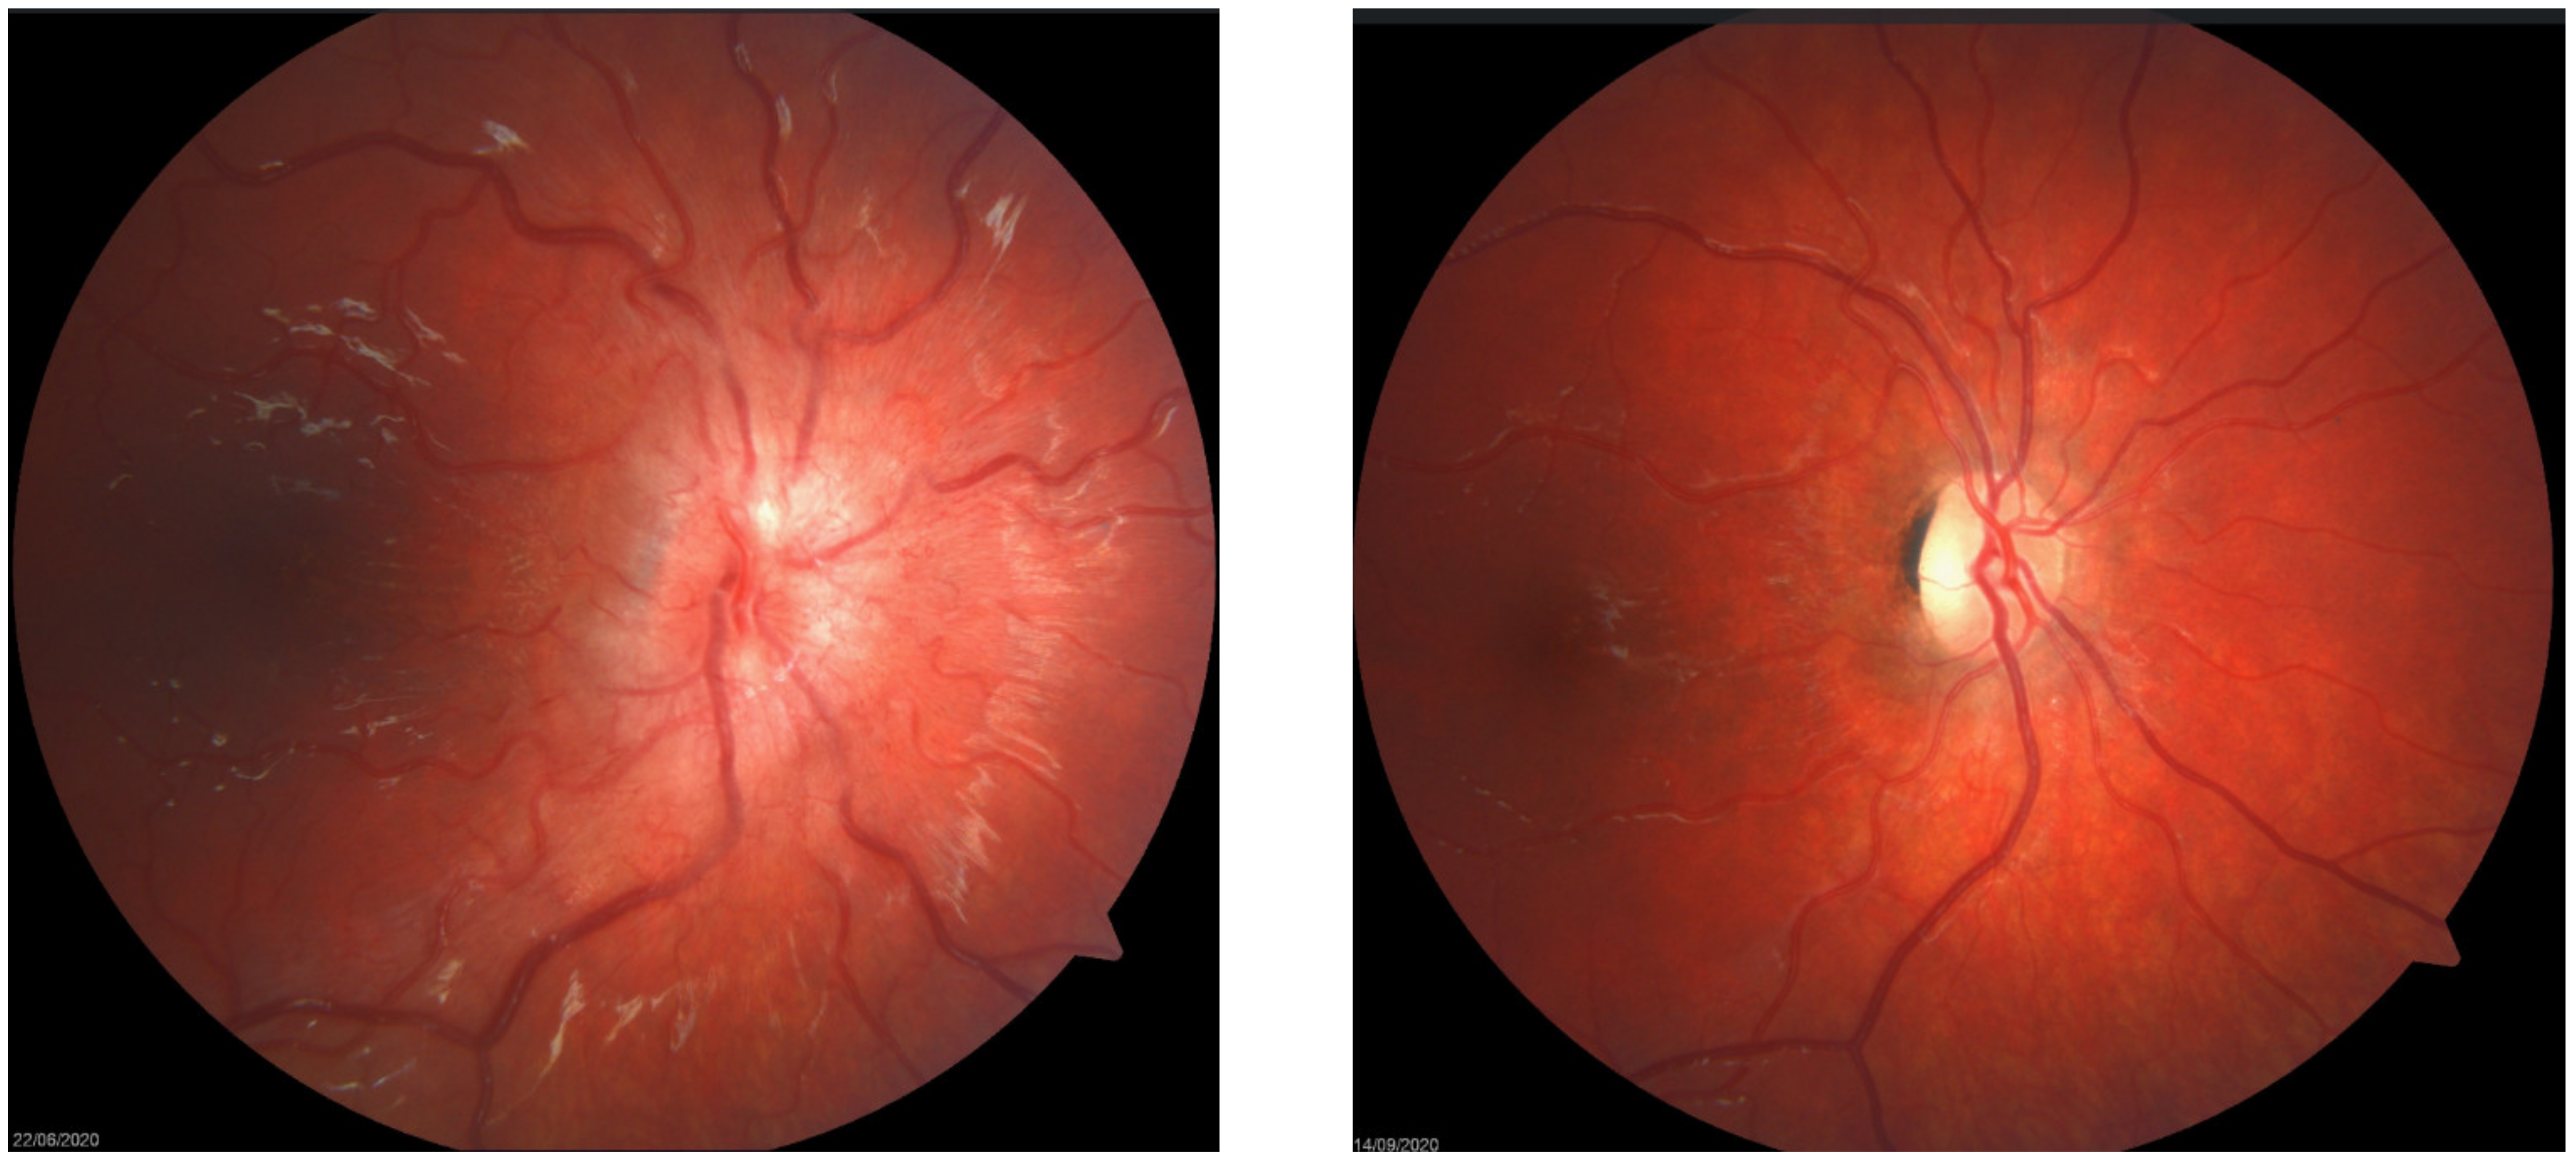

5.2. Signs

- Frisén, L. Swelling of the optic nerve head: A staging scheme. J. Neurol. Neurosurg. Psychiatry 1982, 45, 13–18. [Google Scholar] [CrossRef] [Green Version]

- Gospe, S.M.; Bhatti, M.T.; A El-Dairi, M. Anatomic and visual function outcomes in paediatric idiopathic intracranial hypertension. Br. J. Ophthalmol. 2015, 100, 505–509. [Google Scholar] [CrossRef] [PubMed]